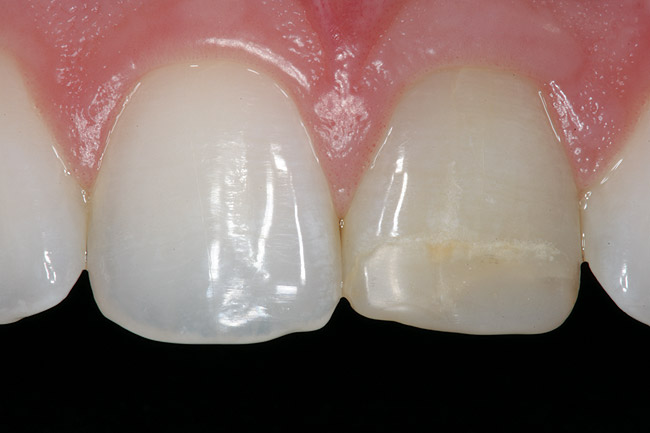

Replacement of existing restorations is responsible for 75% of all operative dentistry.15,19 The reasons for placement and replacement of restorations of direct restorative materials include: primary caries (Figure 1 and Figure 2); recurrent caries (Figure 3); poor margins (Figure 4 and Figure 5); restoration fracture (Figure 6 and Figure 7); tooth fracture (Figure 8); esthetics (Figure 9); non-carious tooth structure lost (attrition, abrasion, abfraction, erosion) (Figure 10); and pain/sensitivity.

Figure 9  Discolored, unesthetic Class IV composite resin on the maxillary left central incisor.

Figure 9